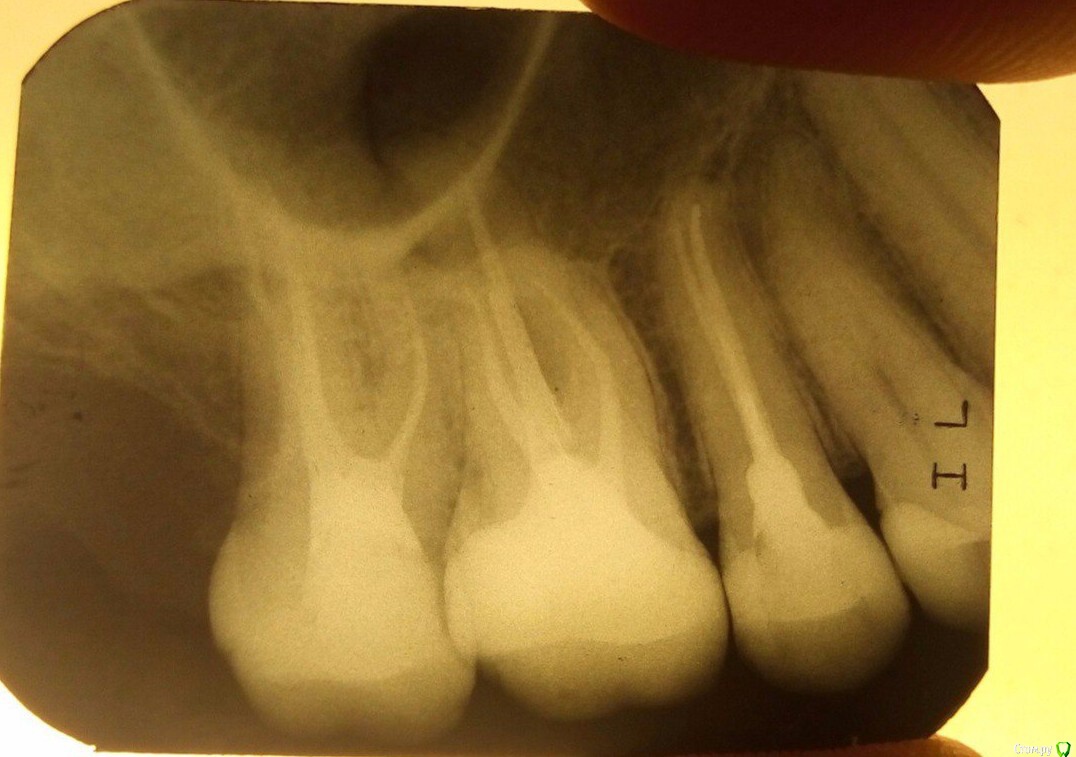

shishok Опубликовано 13 мая, 2017 Поделиться Опубликовано 13 мая, 2017 На пятом пломба временная?Если постоянная,то посмотреть бы фото как минимум. Ссылка на комментарий

ijaija Опубликовано 15 мая, 2017 Автор Поделиться Опубликовано 15 мая, 2017 Вот фото, прикрепил. Ссылка на комментарий

red_butler Опубликовано 15 мая, 2017 Поделиться Опубликовано 15 мая, 2017 Сейчас пятый залечили наложили пломбу, но она не выпуклая как с противоположной стороны, а немного углубленная по форме, это ничего страшного? на фото все нормально с пломбой Или у каждого врача своя пломба?) у каждого пациента свой прикус 1 Ссылка на комментарий